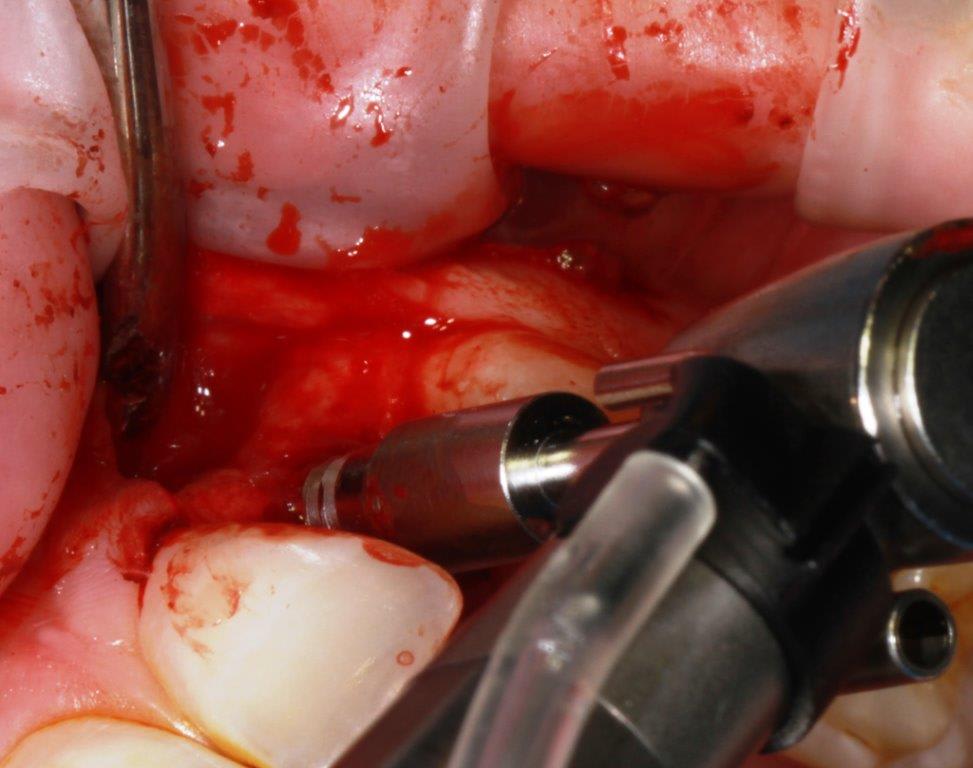

pour ceux que ça intéressent, une petite utilisation d'expansion de la paroi palatine, sur une avulsion d’incisive(racine fendue). toutes mes excuses pour la mauvaise qualité des photos.

Et à ton avis pourquoi ton incisive s'est fendue ? Y a qu'à regarder ta photo ...

Et donc tu mets un Implant dans ce contexte là .... faudra pas se demander pourquoi il y aura des complications prothétiques de type fracture de vis